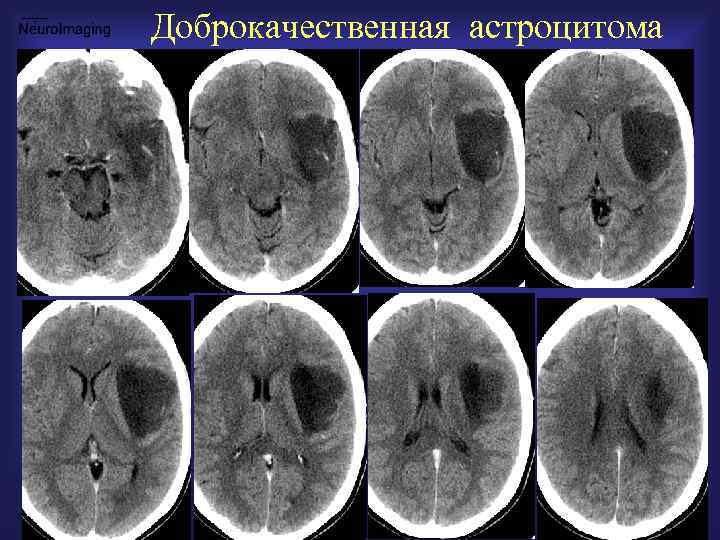

Доброкачественная астроцитома

Доброкачественная АСЦ КТ-гиподенсная КТ-изоденсная